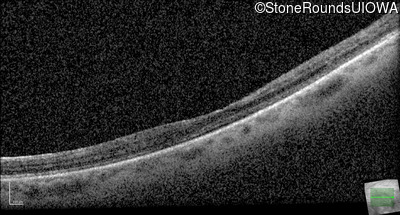

AD Familial Exudative Vitreoretinopathy (IIIE2b)

Age at visit: 32 years

This 32 year old woman has had subnormal acuity (right eye worse than left eye) since very early childhood.

AD Familial Exudative Vitreoretinopathy TSPAN12 Arg50Trp AG(G)>TG(G)   AD